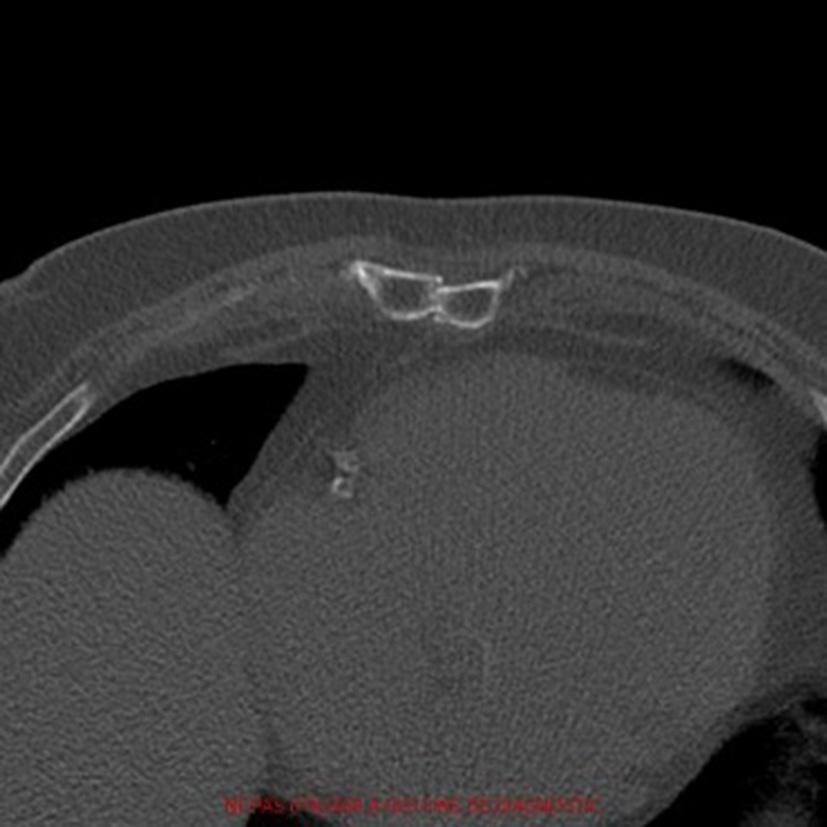

Figure 1

Pre-operative axial computed-tomography image of patient 1. The diagnosis of pseudarthrosis is clear as we can't see any bone bridges between the two halves.